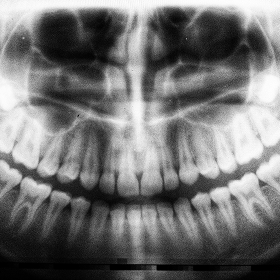

Radiographie panoramique

Imagerie 2D de référence pour un diagnostic éclairé

Vision globale

Notre radiographie panoramique numérique permet une visualisation en deux dimensions claire et exhaustive des structures orales. Cet examen de référence optimise le dépistage global des pathologies, l’évaluation des structures osseuses et dentaires, ainsi que la planification initiale des traitements